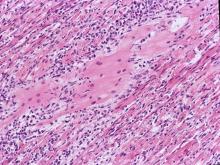

(圖4)。三、 組織病變: 1.

心臟:肌纖維與肌纖維間有大量炎症細胞浸潤,並呈現不同程度之變性、壞死及鈣化

現象(圖6)。2.